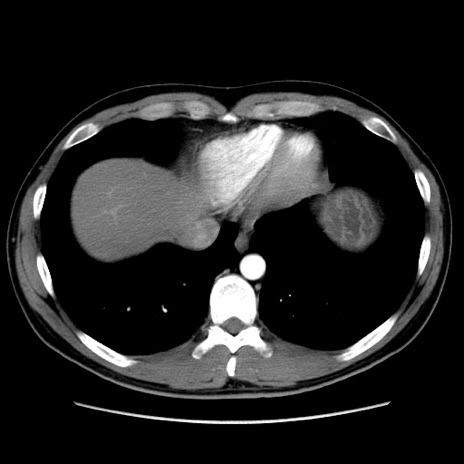

症例36(横断像)

【症例】20歳代 男性

【主訴】心窩部痛

【現病歴】今朝より上腹部痛あり。一旦軽快していたが再度出現したため救急要請。昨日夕に白身の魚を含む刺身を食べた。

【身体所見】BP 136/89mmHg、HR 74/min、BT 37.0℃、腹部:膨満、軟、心窩部に圧痛あり。反跳痛なし、筋性防御なし、腸雑音やや亢進あり。

【データ】WBC 17700、CRP 0.48